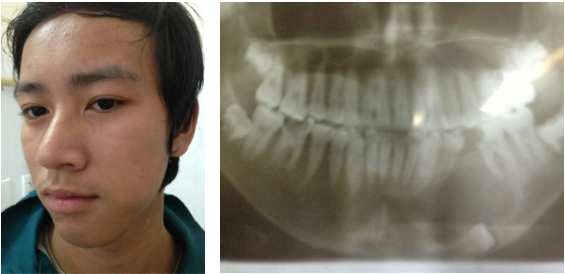

Nang thân răng gây biến dạng mặt trái do R35 ngầm trong xương